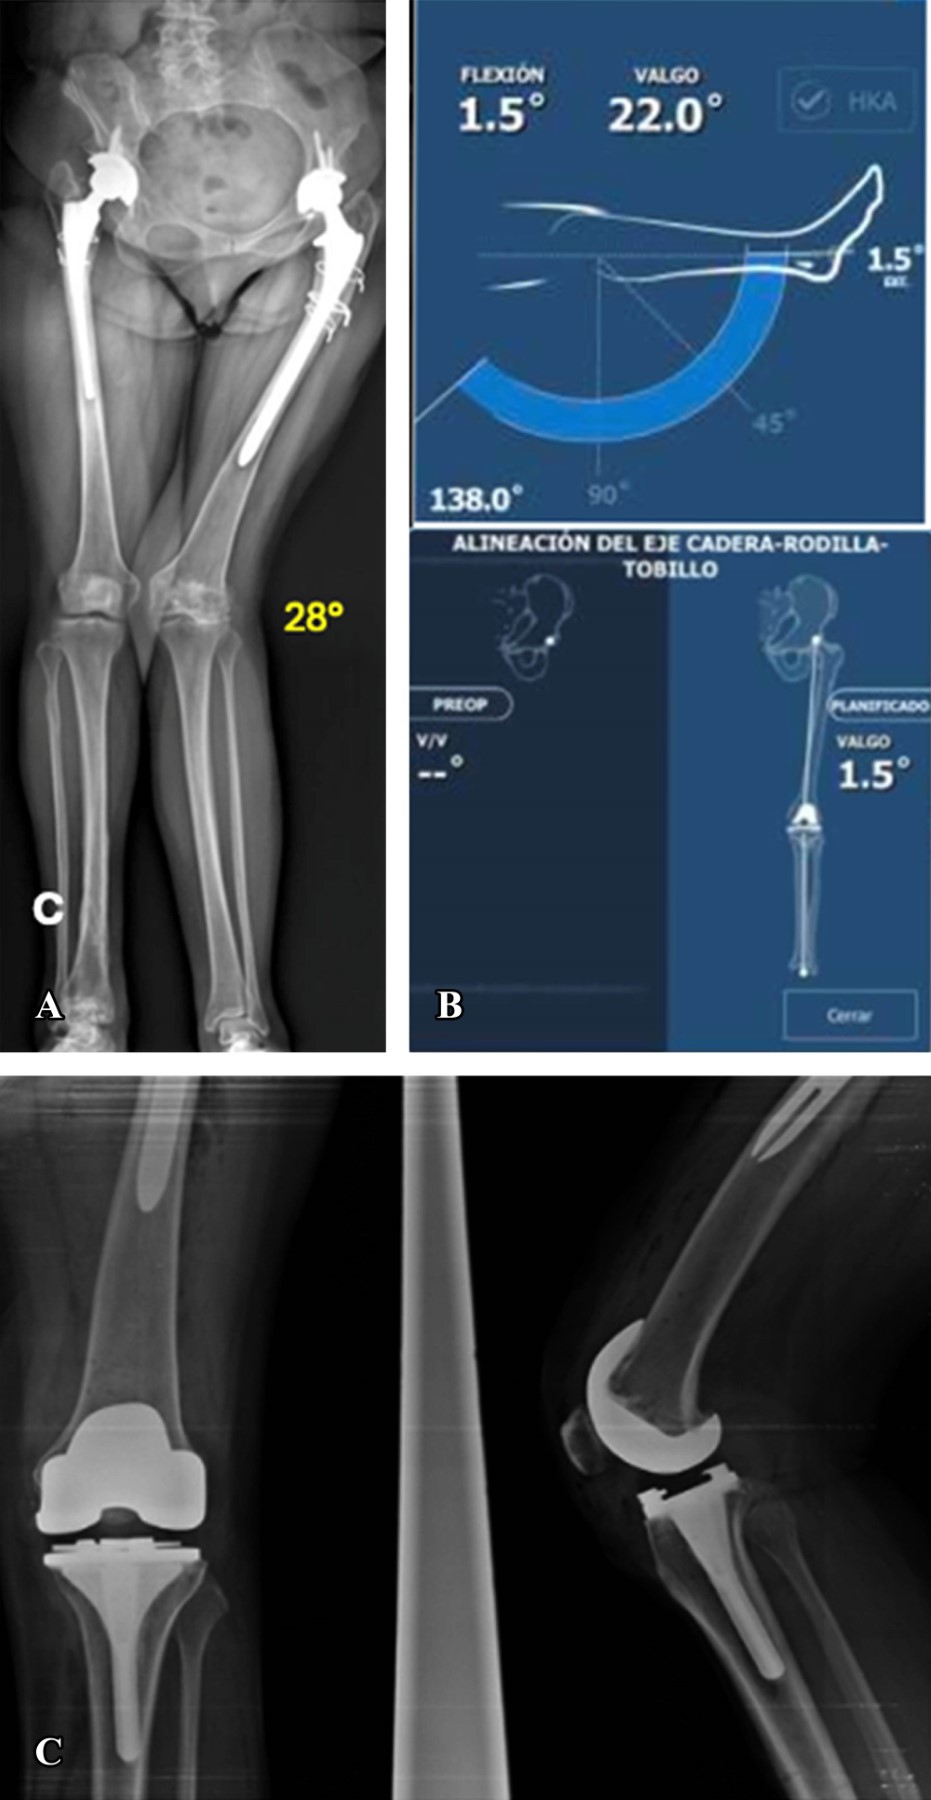

Dieciséis casos presentaron deformidad en valgo (Figuras 2 y 3) con un promedio de 11.88° de deformidad. En cuatro casos la alineación final fue en varo con un promedio 1.87°; en nueve la alineación final fue con un valgo promedio de 1.66° y en tres casos la alineación fue neutra. El cambio en los grados promedio de la serie entre la deformidad inicial y la alineación final fue estadísticamente significativo (p = 0.005) en el análisis de covarianza.

Figura 2